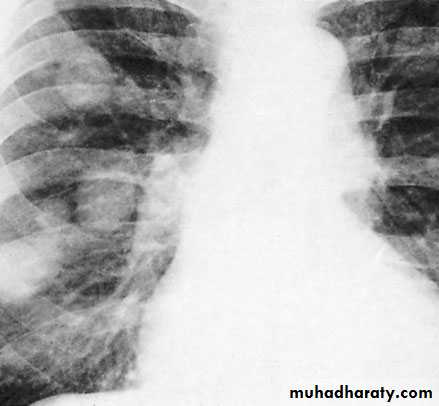

Symptoms of metastatic disease: abdominal or lumbar pain, chest pain, dyspnoea and haemoptysis

CXR: pulmonary metastases especially in teratoma

Scrotal Pathologies